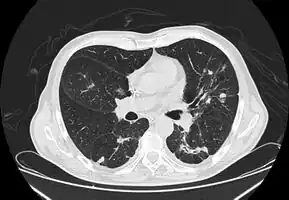

In the juvenile form, lung abnormalities are shown in high-resolution CT scans of the lungs, whereas in the chronic form plain X-rays may show interstitial and alveolar infiltrates in the central and lower lung fields.[14]

CT chest: Paracoccidioidomycosis